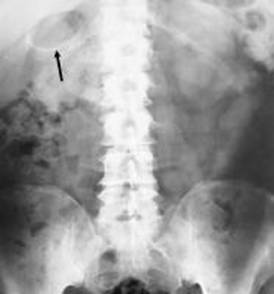

Fig .1 Radiogramma diretto di paziente con colecistite enfisematosa

si noti la presenza di aria nella parete della colecisti

Fig 2 radiogramma diretto dell'addome. Numerose formazioni all'ipocondrio di destra